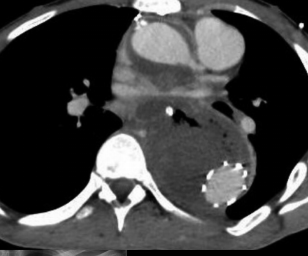

Imagen de portada

Presentamos el caso de un paciente con síndrome de Marfan y varias cirugías de aorta por dicha patología, que sufre de una fístula aortoesofágica, por lo que se traslada a nuestro hospital para tratamiento urgente conjunto por parte de cirugía general y cirugía cardíaca. Sin embargo, fallece antes de poder llevarlo a quirófano.